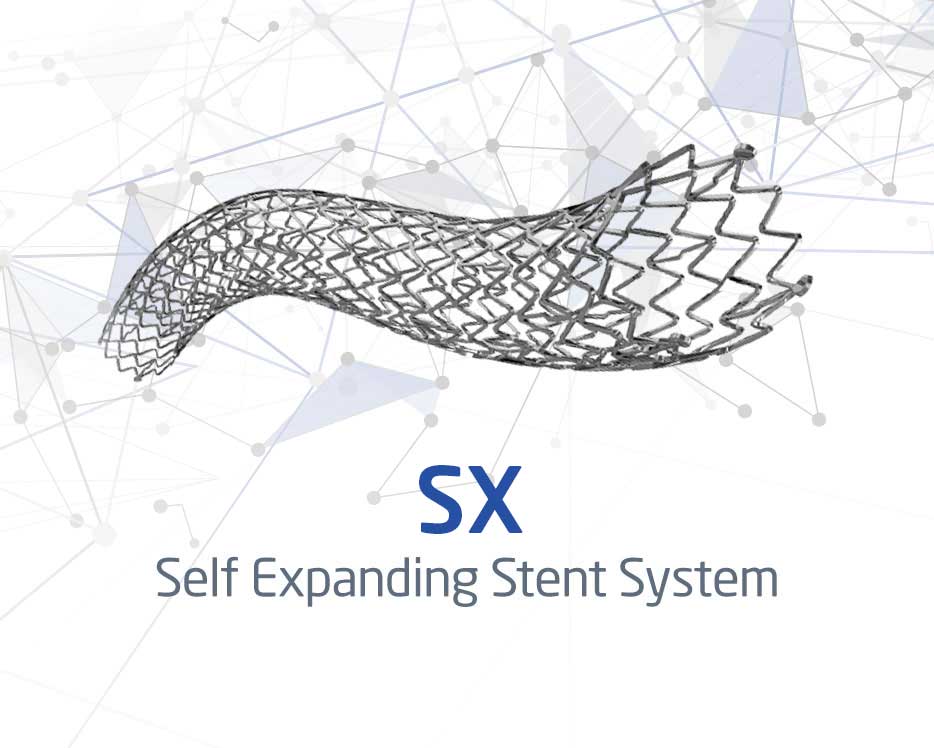

Self Expanding Stent System

See Product